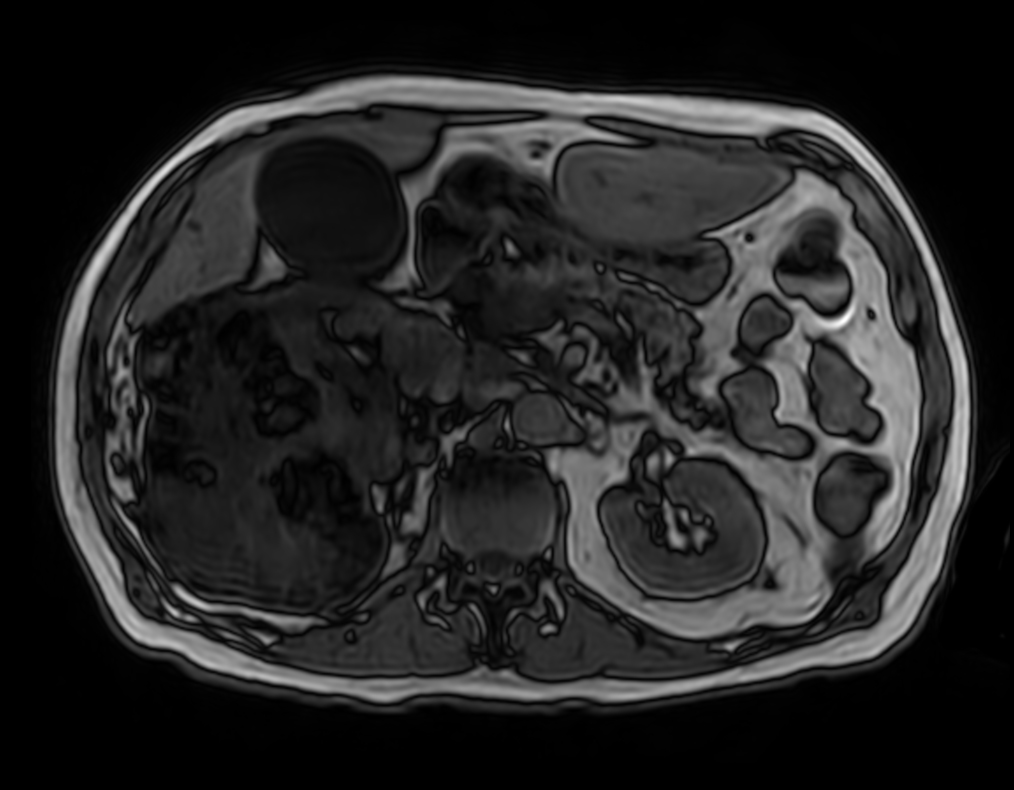

Patient with kidney tumor. ExamCard includes Compressed SENSE to shorten the breath hold time, VitalEye for touchless respiratory sensing, mDIXON XD FFE to acquire up to four image types in one single scan, DWIBS to achieve high contrast between background and lesions and bTRANCE for non-contrast time-resolved imaging.

T2w SPAIR - VitalEye Compressed SENSE

T2w TSE - VitalEye Compressed SENSE